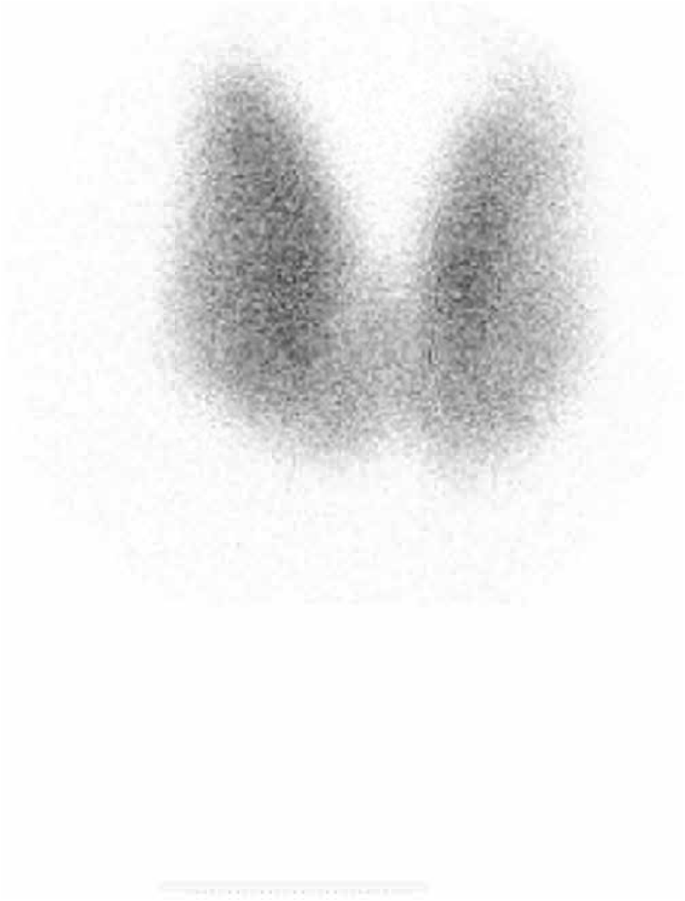

A technetium-99 m pertechnetate thyroid uptake scan demonstrated homogenous diffuse tracer uptake in both lobes in keeping with a diagnosis of Graves’ disease (Fig. 1.). Sex hormone binding globulin was 92 nmol/l (27–128).